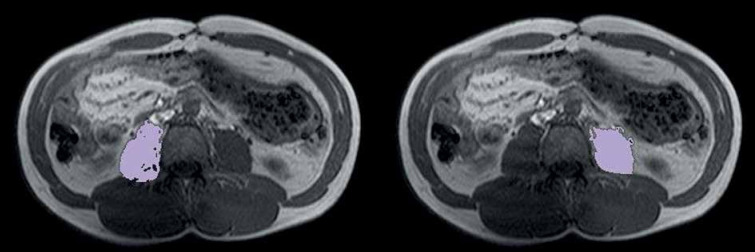

Material and methods: This was a retrospective study of 88 CD patients who underwent magnetic resonance enterography. Patients were classified according to the Montreal Classification in uncomplicated (non-stricturing, non-penetrating, B1), and complicated (structuring [B2] and penetrating disease [B3]). At the level of the third lumbar vertebra, the ADC and PMI were estimated. CD activity was analysed using the Magnetic Resonance Index of Activity (MaRIA), and depending on its values patients were categorized as high or low activity. Additionally, the presence of creeping fat (CrF) was used to evaluate activity. ADC and PMI were using Student's t-test.

Results: Our study included 47 males and 41 females (mean age of 38.69 ±14.4 years). The ADC in uncomplicated (B1, n = 45) and complicated disease (B2 + B3, n = 43) were 1.11 ±0.19 and 1.03 ±0.10 (10-3*mm2/s), respectively, (p = 0.02). ADC was significantly lower in patients with stricturing disease than in patients without strictures (1.02 ±0.11 and 1.10 ±0.18 [10-3 mm2/s], respectively, p = 0.01). The group with non-penetrating disease showed higher PMI than those with penetrating disease (5.71 ±1.88 vs. 4.42 ±1.55 cm2/m2, respectively, p = 0.10). There was no significant difference in PMI and ADC between patients with low and high MaRIA or positive and negative CrF.

Conclusions: The ADC of the psoas muscles is significantly lower in CD patients with uncomplicated disease, particularly those with stricturing disease. Therefore, ADC can be considered as an imaging biomarker of myopathic changes in CD patients.